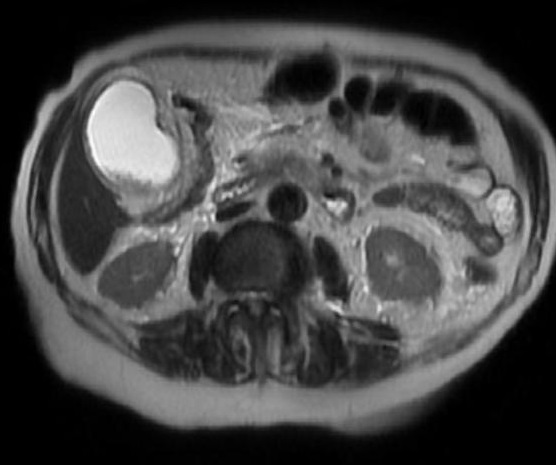

Vesicule biliaire

hyperintense distendue, paroi epais et oedeme

: Image radiologique IRM ponderee en T2 , Coupe

axiale |

Meme cas en coupe IRM

coronal T2 |